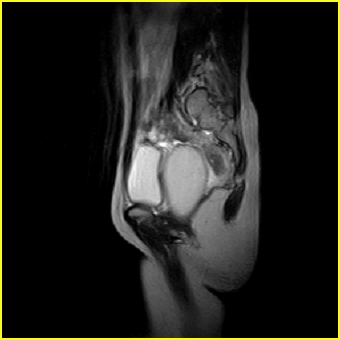

女、15岁、下腹疼痛2天,排尿困难1天。查体:处女膜闭锁,距处女膜约4至5cm处扪及一约5cm直径的圆形包块,张力较高,触痛明显、欠活动。b超提示子宫增大伴宫内增强回声团。

影像意见:子宫直肠陷凹积血。

更正影像意见:阴道积血。

处女膜闭锁,阴道积血

处女膜闭锁,阴道积血,子宫积血.

阴道积血,子宫积血.

子宫及阴道积血。

处女膜闭锁,伴子宫及阴道积血.